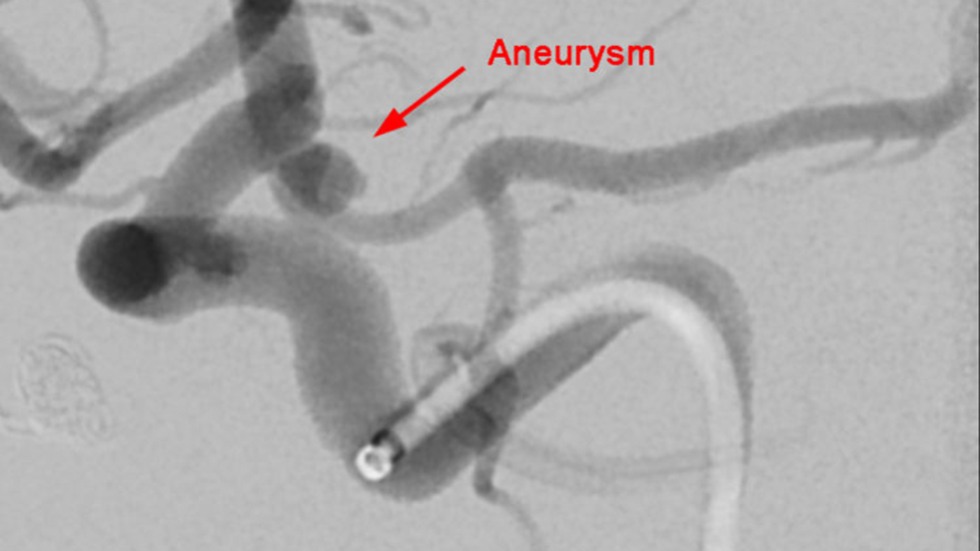

Primary Coil Embolization, Technique: Aneurysm

1 of 3

Primary Coil Embolization: Treats aneurysm from the inside rather than the outside. Fill aneurysm with embolic coils in order to obliterate blood flow.

Technique: Coil

2 of 3

Technique: Treated Aneurysm

3 of 3